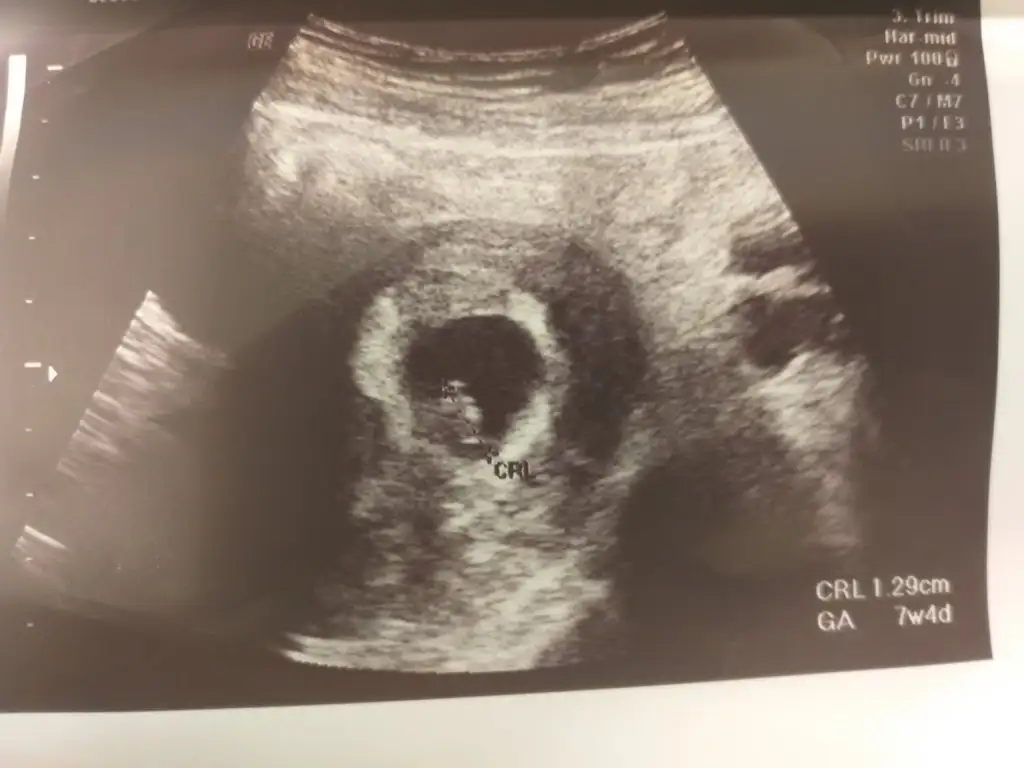

2.resim 7 haftalik karindan usg